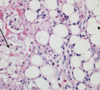

Grossly, acute pancreatitis will present with _

Grossly, acute pancreatitis will present with **swollen, edematous pancreas** with **fat necrosis** and **hemorrhage**

Explain the saponification of fat in acute pancreatitis

Inflammation mediated by neutrophils --> **adipocytes get necrotic and release fatty acids** --> **fatty acids bind to calcium** --> calcium soaps